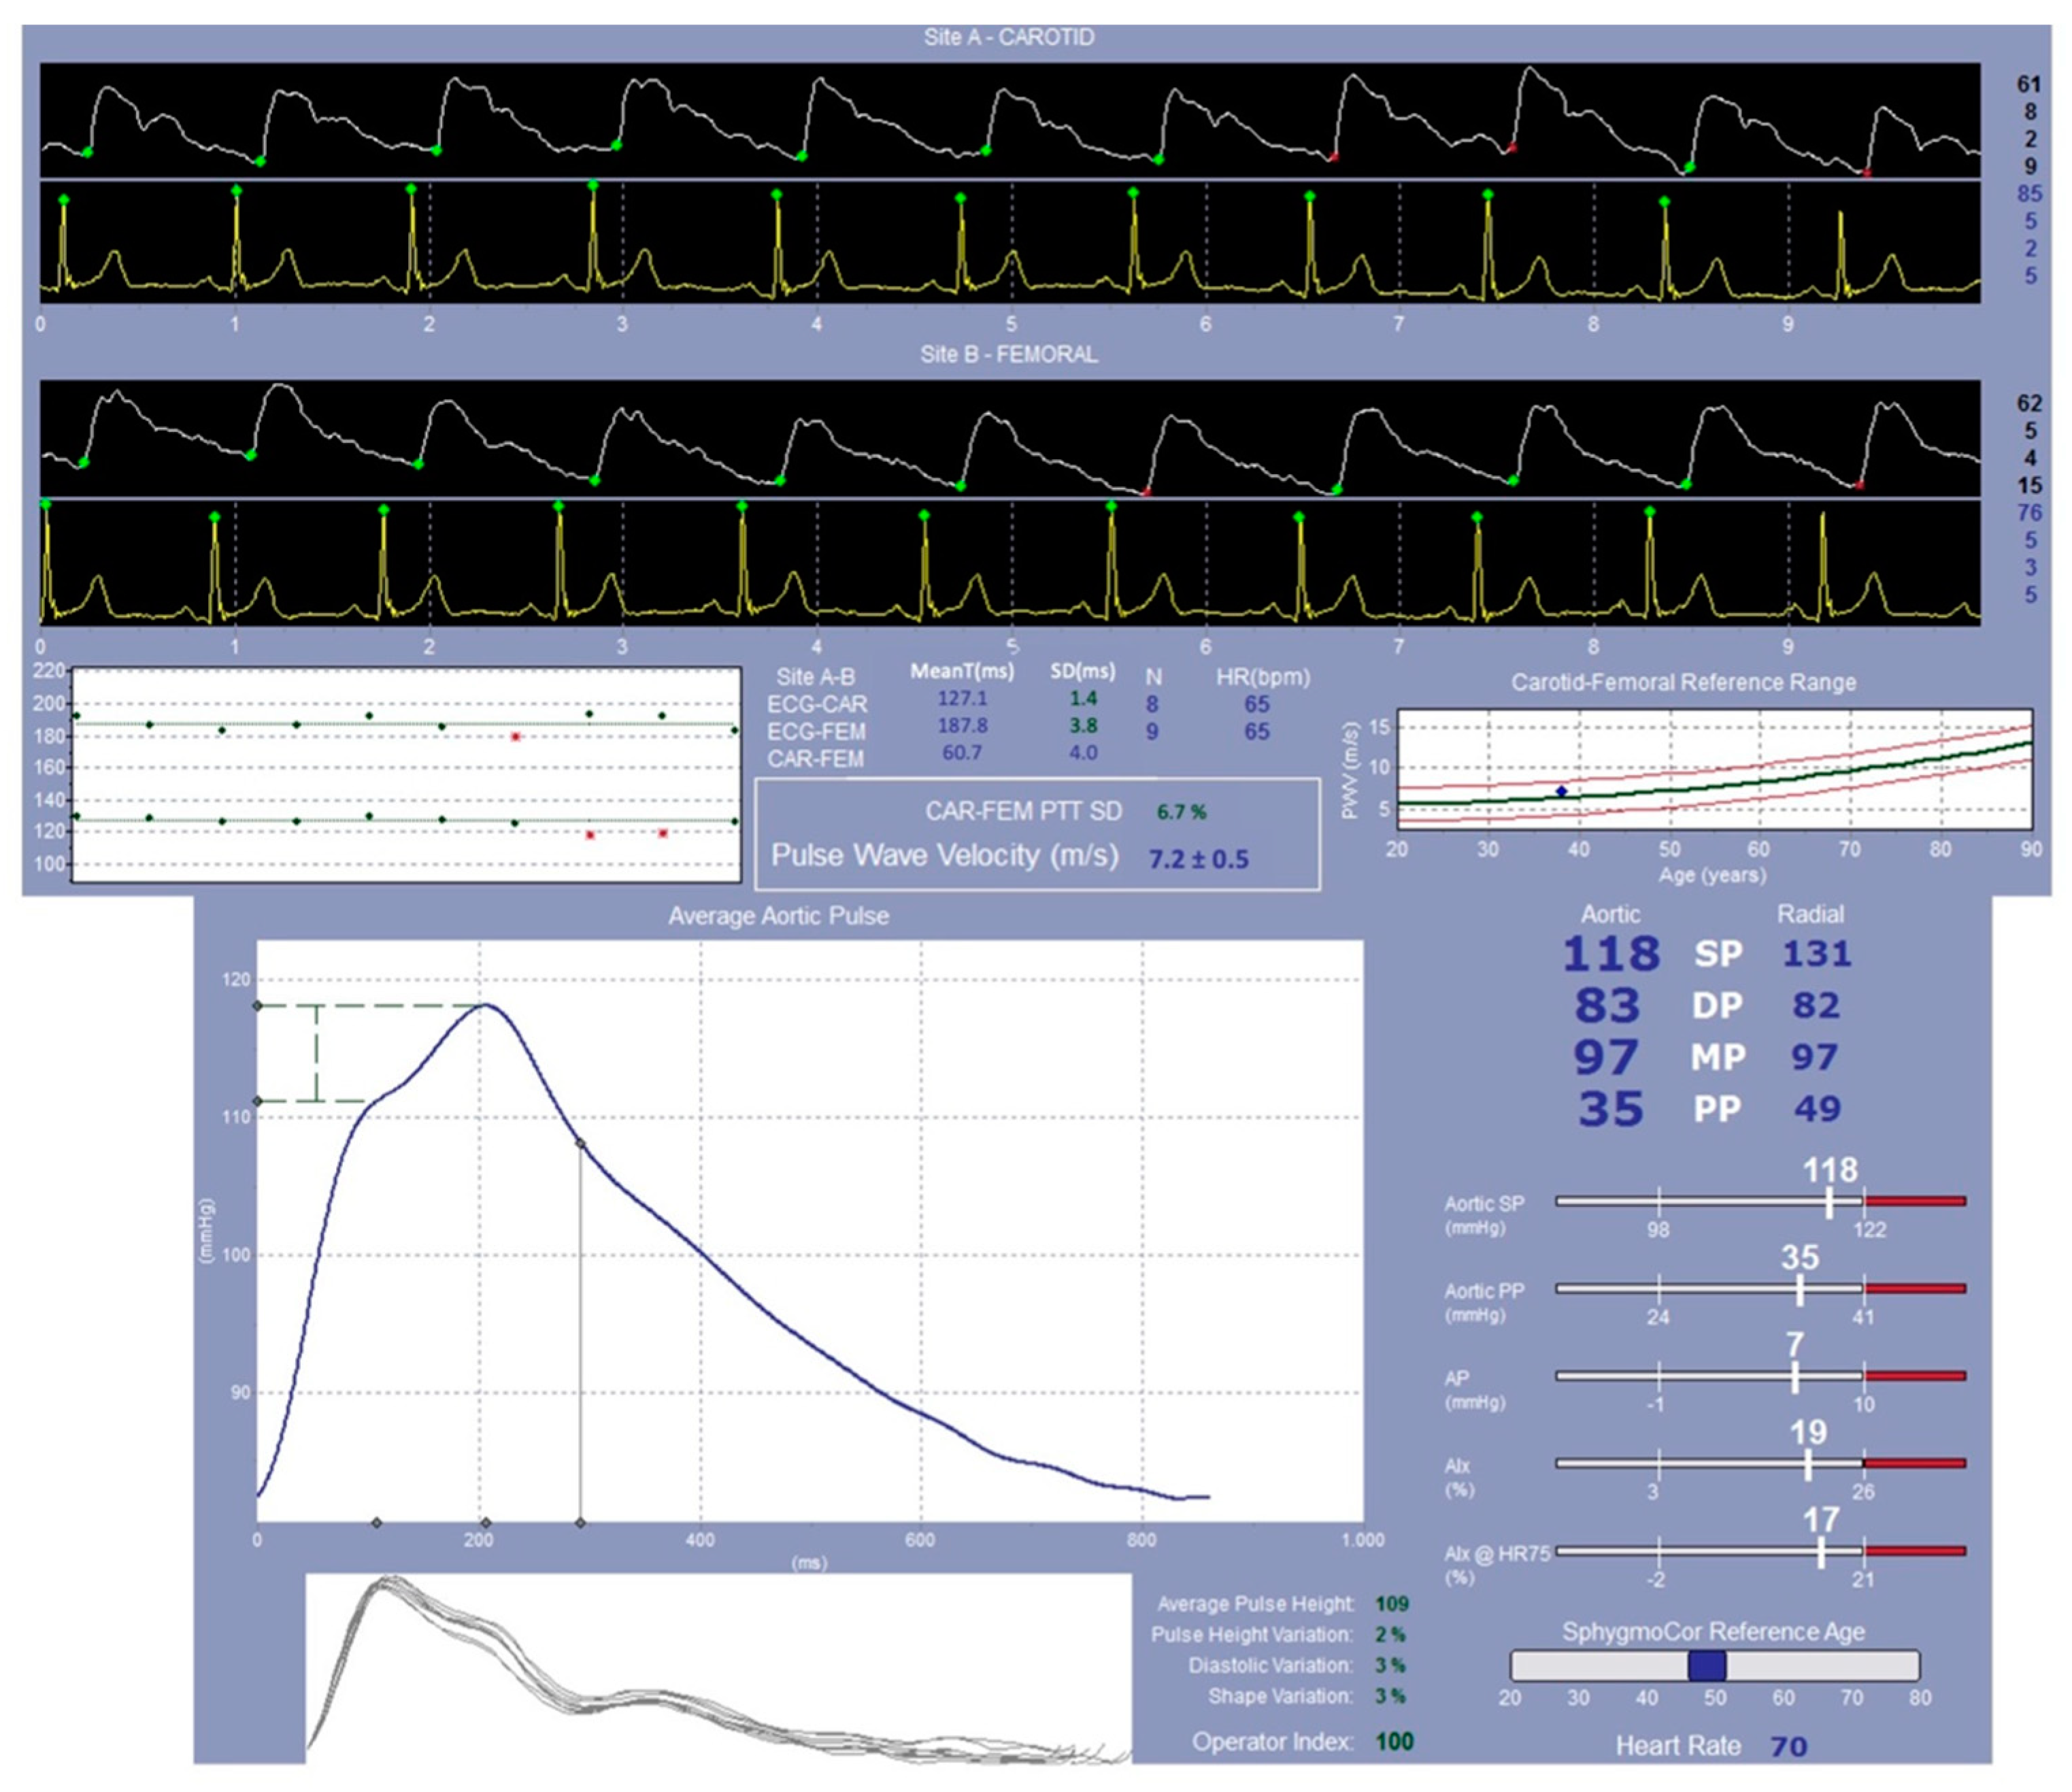

4.4.2. SphygmoCor System Evaluation: Study of the Pulse Wave Velocity

- Butlin, M.; Qasem, A. Large Artery Stiffness Assessment Using SphygmoCor Technology. Pulse 2017, 4, 180–192. [Google Scholar] [CrossRef]

| Pulse wave velocity | Cardiological evaluation (SphygmoCor system) | N/A | T0 and T1 |